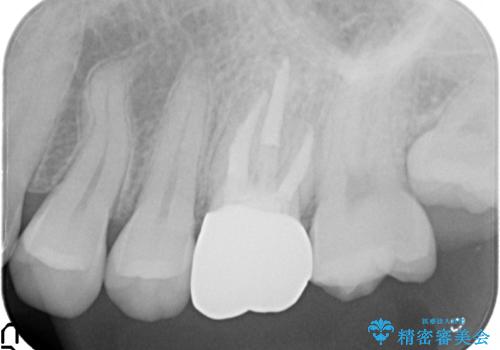

金属の奥歯 → 白い奥歯 根管治療からのやり直し

- 再根管治療→土台の築造 を行った上でのかぶせ物のやり替えをおこないました。

神経の無い歯のかぶせ物をやり替える際は、是非根管治療からしっかりやり直すことをおすすめします。

かぶせ物の種類:Bellezza